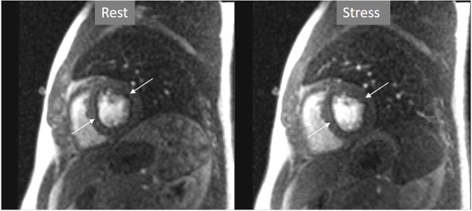

Important for a reliable identification of perfusion defects is the recognition of artifacts that may mimic a true defect which, unfortunately, are frequent, even with advanced MR systems. The most relevant is the so-called “dark-rim artifact”, which consists on a subendocardial, sharp linear signal of very low intensity that is due to magnetic susceptibility effect, to spatial resolution, and/or to motion effects [43, 44]. This dark band may appear as soon as the contrast arrives to the left ventricular chamber, is usually very thin (1–2 pixel wide), transient, and can be present at both the rest and stress studies [40] (Figs. 11,12). Despite these hints, cases where an artifact occasionally challenges the judgement of the observer still persist (Fig. 13).

Fig. 12.Perfusion artifact. Dark-rim artifact present at both stress and rest studies (arrows).

Fig. 13.Perfusion artifact. Artifactual stress perfusion defect (arrows) not present at rest, leading to angiography which did not show CAD (right panels).